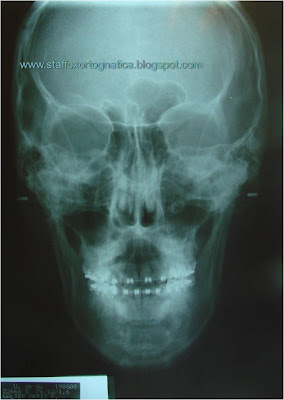

A. ANÁLISIS FRONTAL

Simetría: presenta predominio transversal derecho.

Plano oclusal simétrico

Línea media dental superior coincide.

Línea media dental inferior desviada 1.3mm a la izquierda.